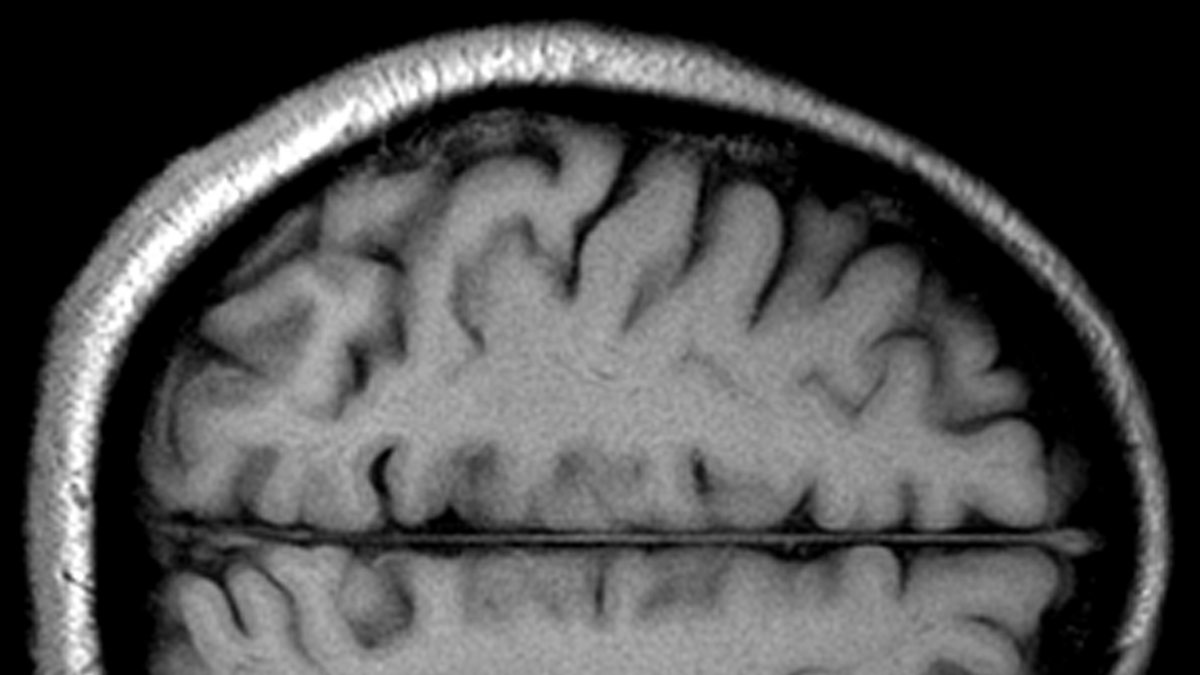

1976: Mind over matter

A young Colin Blakemore's Reith Lecture: Understanding the human brain is more important than understanding the frontiers of space or the inside of an atom.